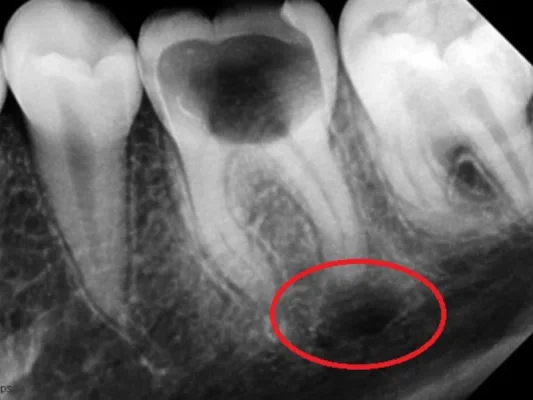

- Radyolojik tetkikler: Diş röntgenleri, bilgisayarlı tomografi (CT) veya manyetik rezonans görüntüleme (MRI) gibi radyolojik tetkikler yapılabilir.

Diş kökü lezyonu:

- Diş köklerinde ağrı, şişlik, apse veya enfeksiyon görülür.

- Genellikle diş çürükleri, travma veya endodontik problemlerden kaynaklanır.

- Diş kökü enfeksiyonları olarak da bilinir.

- Tedavisi, kanal tedavisi veya diş çekimi gibi cerrahi işlemler gerektirebilir.